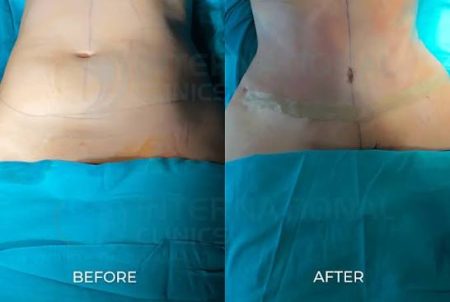

أظهر تحليل بيانات أكثر من 4300 مريض مصاب بسرطان الكبد أن أولئك الذين خضعوا لعملية زراعة الكبد أو استئصال الورم جراحياً بعد تلقي العلاج المناعي، حققوا بقاءً أطول بشكل ملحوظ. العلاج المناعي يعمل على تقليص حجم الأورام، لكنه في حد ذاته لا يقضي على المرض بشكل كامل. ومع ذلك، عندما يتيح هذا الانكماش إجراء جراحة أو زراعة، فإن خطر الوفاة الإجمالي ينخفض بنسبة تصل إلى 85٪ مقارنةً بالمرضى الذين يعتمدون على العلاج المناعي وحده، وفقًا للدراسة.

على الرغم من الفعالية الواعدة لهذا المزيج العلاجي، فإن نسبة المرضى الذين يتم توجيههم للخضوع للعمليات الجراحية بعد العلاج المناعي لا تزال منخفضة، حيث تبلغ حوالي 3٪ فقط. ويرجع ذلك بشكل كبير إلى أن هذه العمليات غالبًا ما تُجرى في المراكز الطبية الأكاديمية الكبيرة والمتخصصة، مما يحد من إمكانية الوصول إليها بالنسبة للعديد من المرضى. بالإضافة إلى ذلك، قد يواجه الأطباء تحديات في تحديد المرضى الذين من المرجح أن يستفيدوا من هذا النهج.